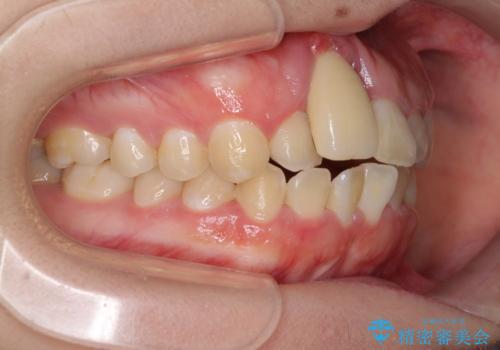

- 中学生の頃にぶつけた前歯に不格好なクラウンが装着されており、出っ歯な印象になっていることを気にして来院された患者様です。

ぶつけてしまった歯は保存が困難な状況であったので抜歯をし、ワイヤー矯正により歯列を整えつつ前歯の突出感を解消することとしました。

前歯の補綴治療はインプラントかブリッジかで悩んでいました。

周りの歯にむし歯がないため、インプラントがお勧めとなりますが、事故による骨欠損が大きく、歯肉ラインを整えるのが困難という問題がありました。